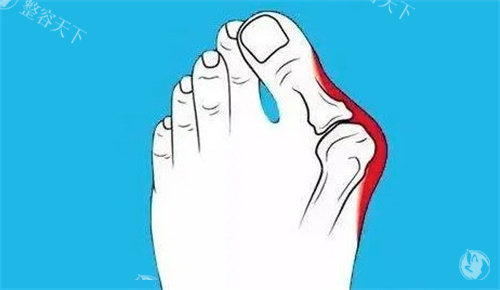

困扰多年的双脚难题

我的双脚大脚趾根部长期以来一直向外突出,形成难看的骨凸。不仅穿鞋经常磨脚,走路时间稍长就会隐隐作痛。每到夏天,我总是避免穿凉鞋,担心别人看到我变形脚型的异样眼光。这种困扰像块沉甸甸的石头压在我的心头,让我渴望找到解决之道。

接诊的医生经验充足且态度和蔼。他仔细检查了我的双脚,让我做了一些简单动作来观察脚部活动情况,还结合X光片详细解释了拇外翻的形成原因和发展程度。这种正规的讲解让我对自己的病情有了清晰认识,也对后续治疗增添了信心。